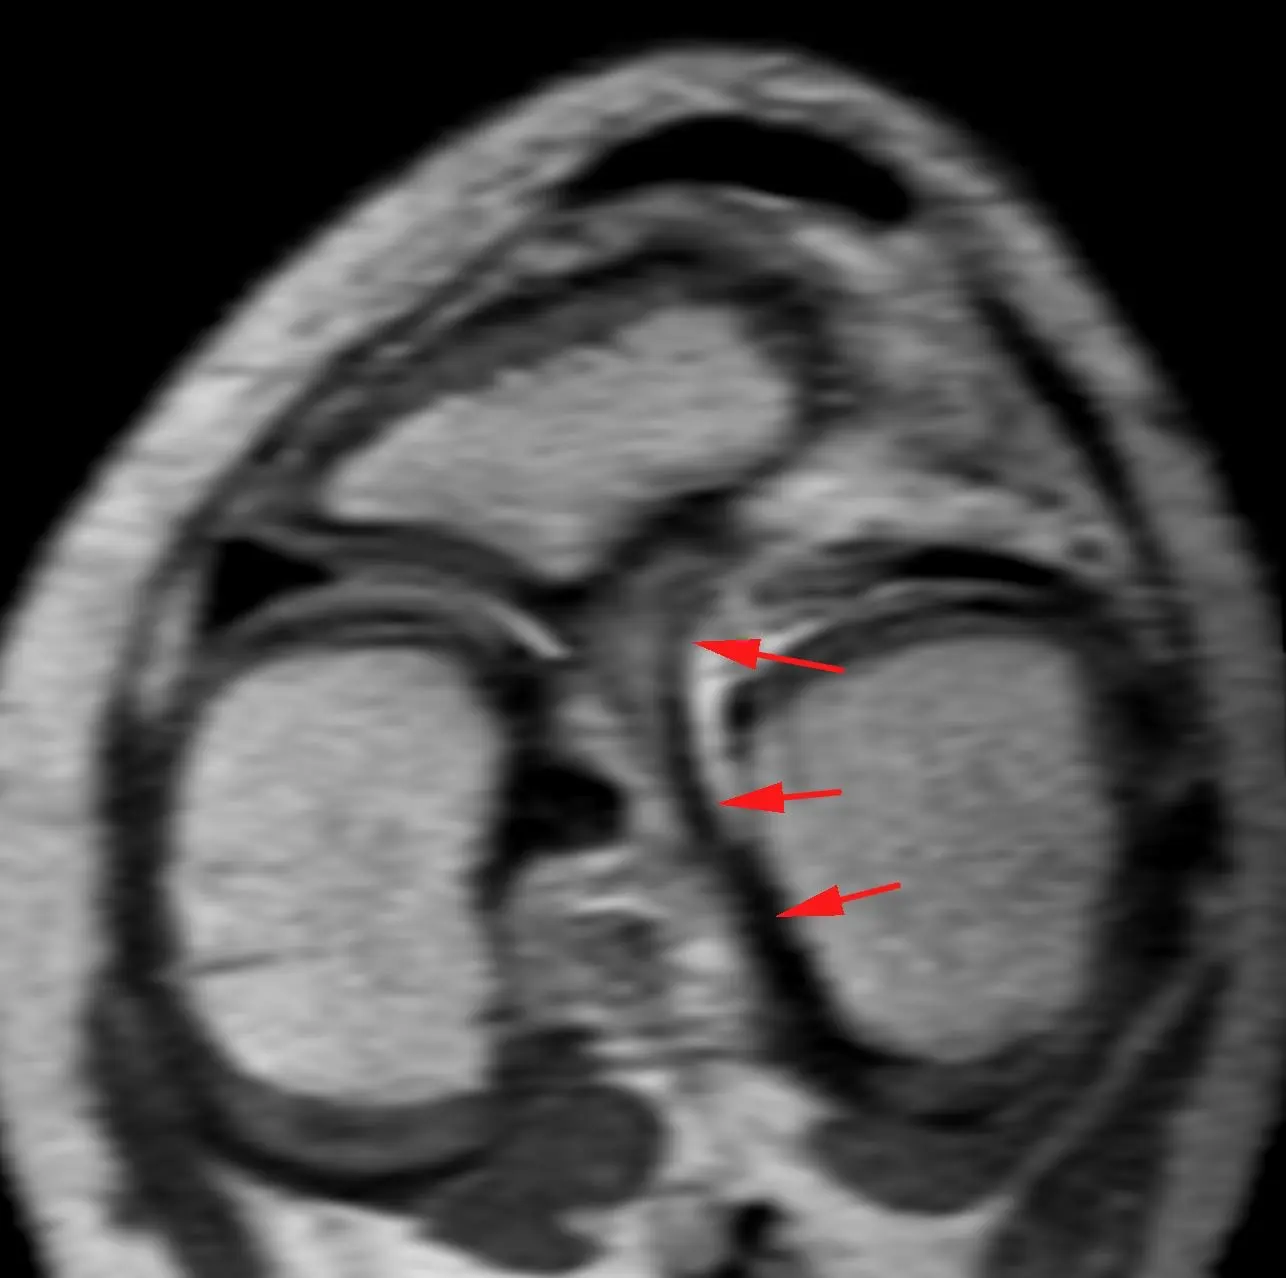

Обширная, ветвистая венозная мальформация (ранее известная, да и до сих пор тоже, как гемангиома) мягких тканей области коленного сустава.

Картина типичная, дифференциальная диагностика не требуется.

Представляет собой скопление аномальных, расширенных, извитых венозных сосудов, стенка которых гистологически не отличается от стенок обычных вен. Хорошо видны связи мальформации с обычными венами. Внутри некоторых из полостей видны выпадение сигнала, которые являются флеболитами (кальцинированными внутрисосудистыми тромбами).

Кстати, может никак не проявляться клинически, будучи даже таких больших размеров.